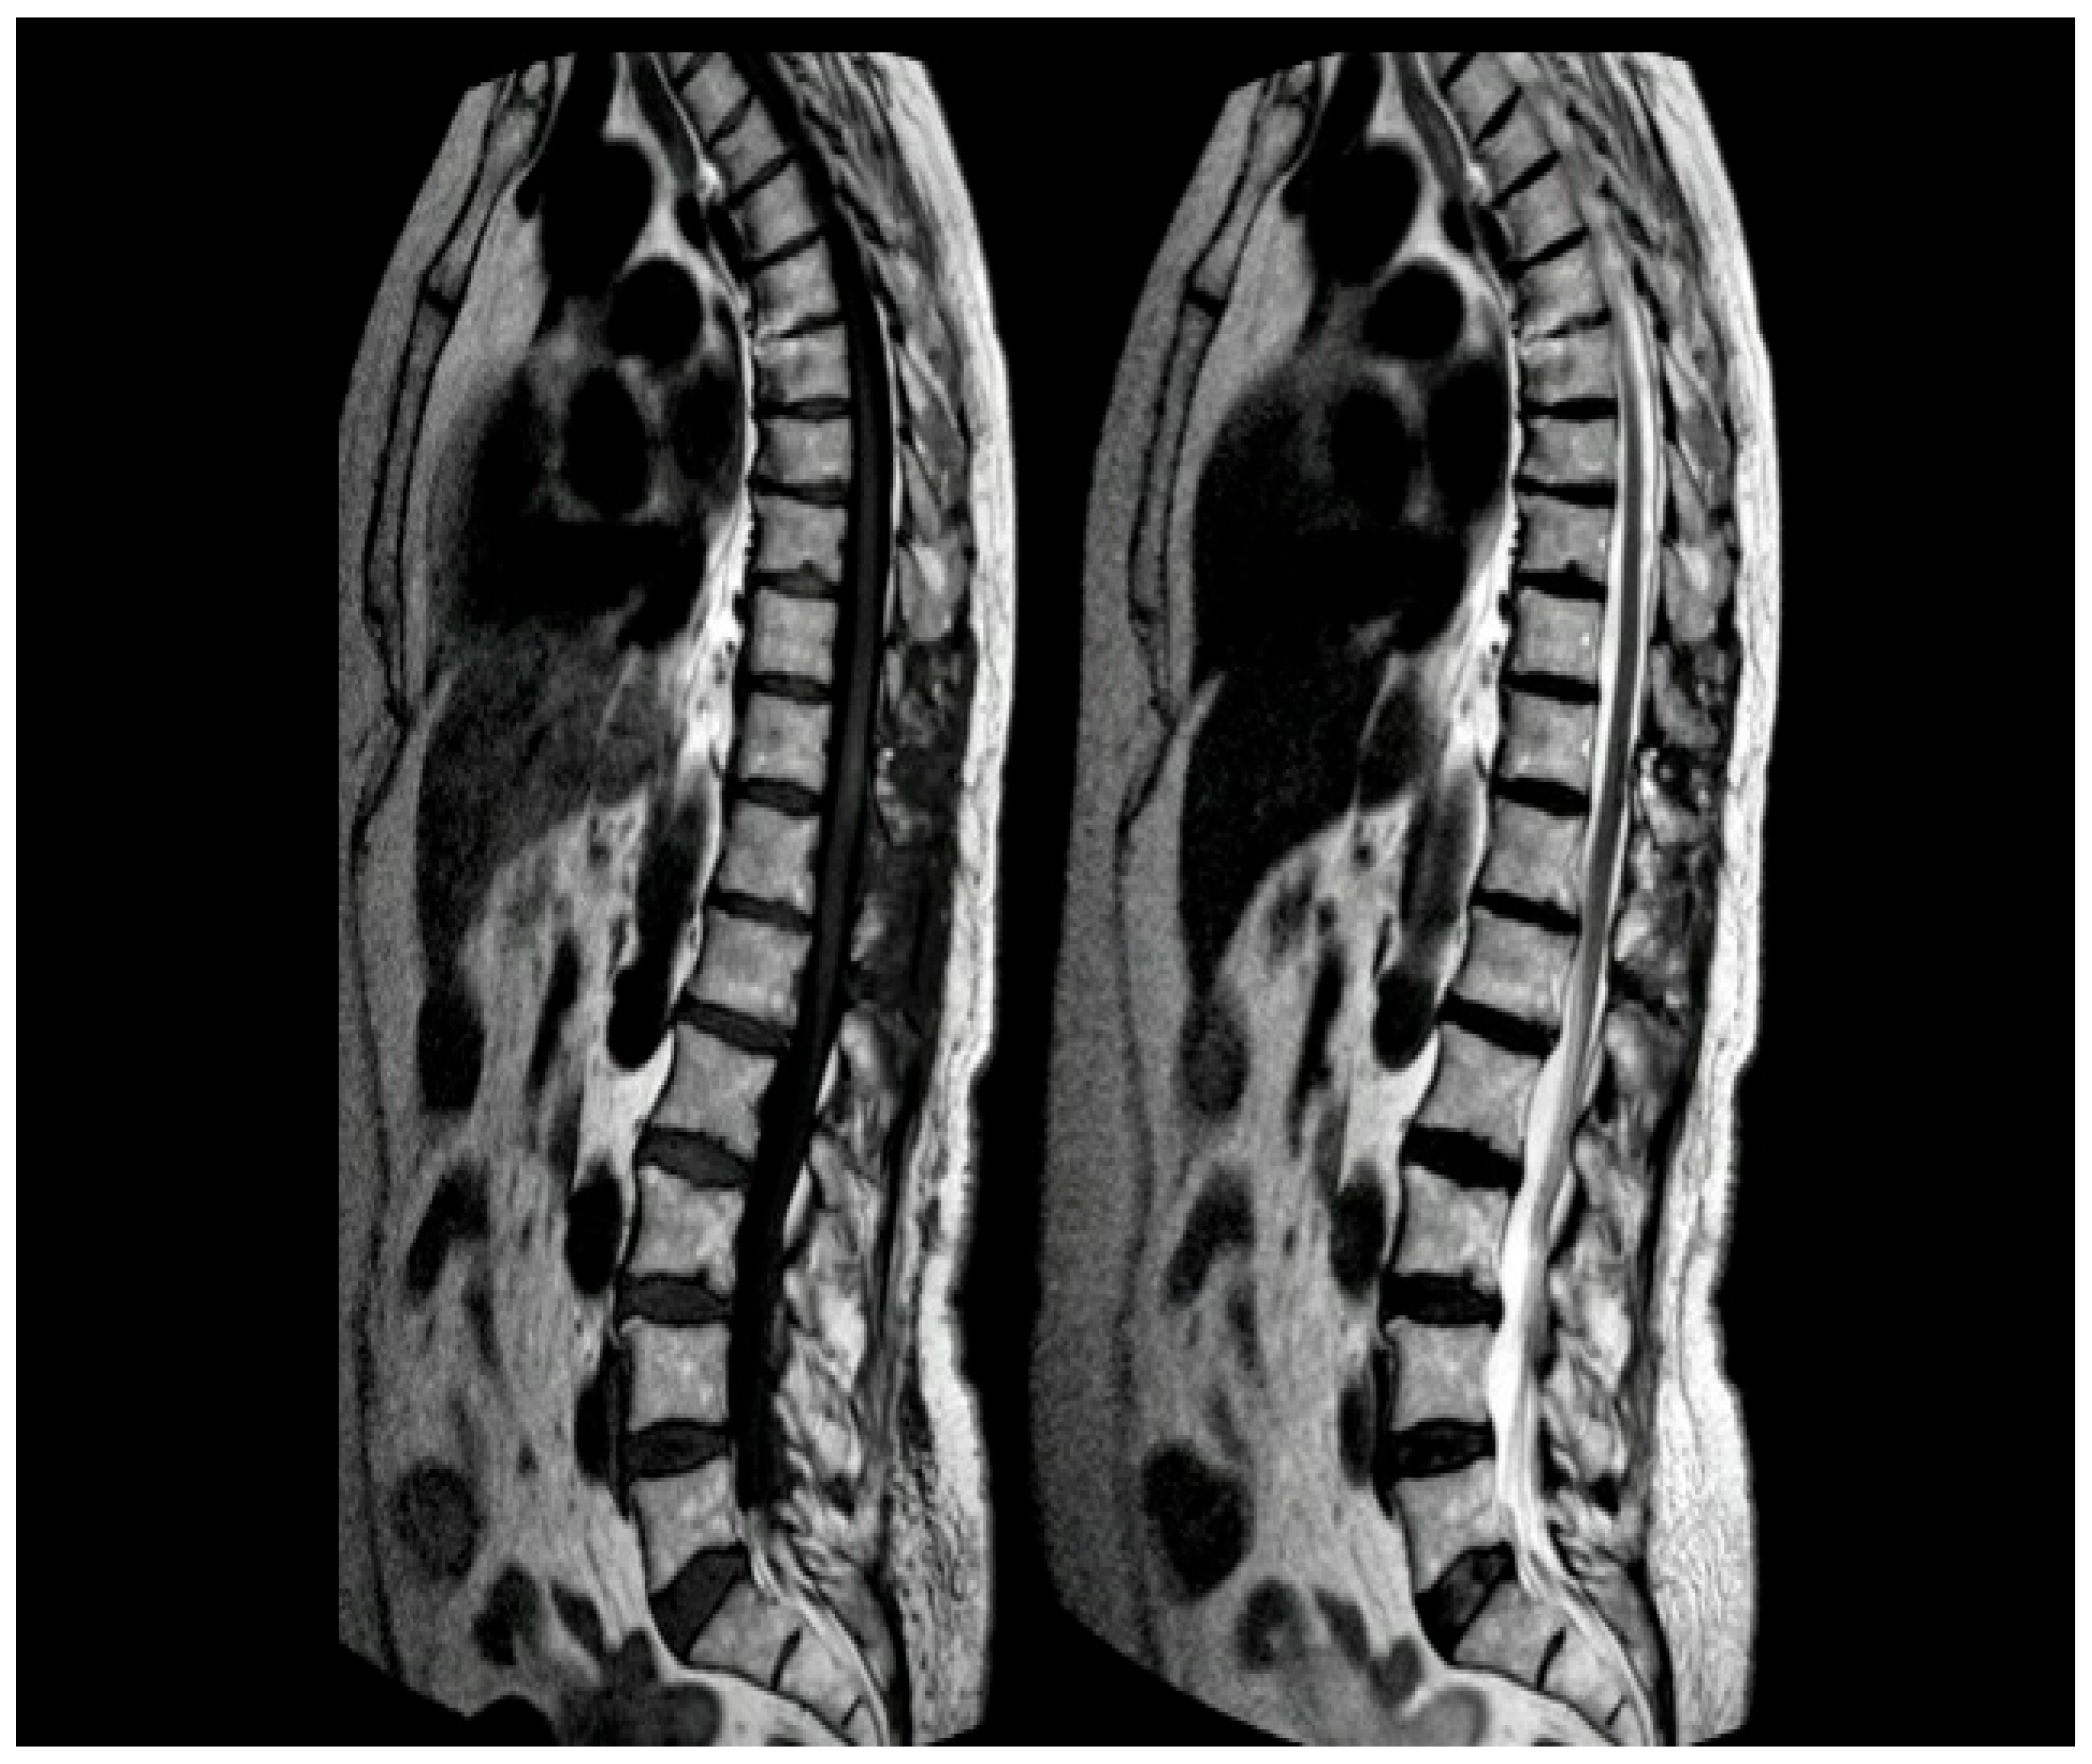

A contrast-enhanced MRI was performed at 3 months, demonstrating the absence of residual pathology [Figure 5].

Figure 5.

Post-operative MRI of the thoracic spine at 3 months. Left: T1-weighted image showing the absence of hyperintense findings. Right: T2-weighted image showing edema resolution.